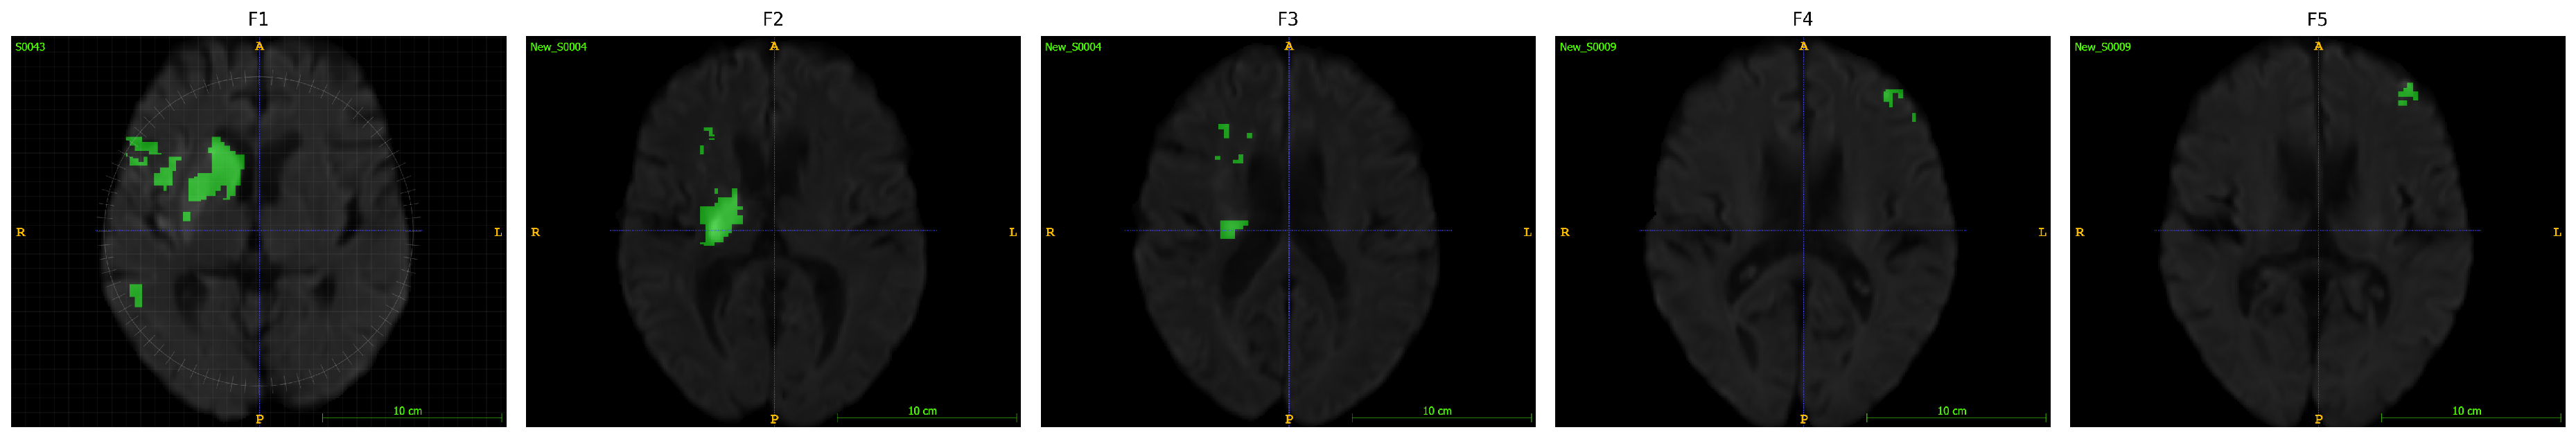

3.1. Machine Learning-Driven Stroke Lesion Segmentation with ATLAS Dataset